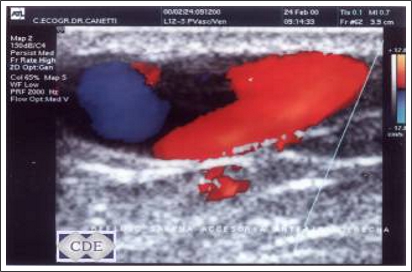

Es un estudio que permite diagnosticar alteraciones venosas (várices), arteriales (trombosis) de miembros inferiores, superiores y de los vasos del cuello. Es totalmente incruento pues es superficial, no necesita ninguna preparación y presenta una efectividad diagnostica altamente satisfactoria. Lo efectuamos en nuestro Centro diariamente.